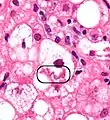

NASH (inflammation) and fibrosis stage 1

NASH (inflammation) and fibrosis stage 2

Lobular inflammation

The primary characteristic of NAFLD is the accumulation of lipids in the liver, largely in the form of triglycerides.[13] However, the mechanisms by which triglycerides accumulate and the reasons that accumulation can lead to liver dysfunction are complex and incompletely understood.[13][28][29][30] NAFLD can include steatosis along with varied signs of liver injury: either lobular or portal inflammation (a form of liver injury) or ballooning degeneration. Similarly, NASH can include histological features such as portal inflammation, polymorphonuclear cell infiltrates, Mallory bodies, apoptotic bodies, clear vacuolated nuclei, microvesicular steatosis, megamitochondria, and perisinusoidal fibrosis.[12] NASH increases hepatocyte death via apoptosis or necroptosis is increased in NASH compared with simple steatosis, and inflammation is a hallmark of NASH.[24]

NAFLD comprises two histological categories: NAFL, and the more aggressive form NASH. The presence of at least 5% fatty liver is common to both NAFL and NASH, but the features of substantial lobular inflammation and hepatocyte injuries such as ballooning or Mallory hyaline only occur in NASH. The majority of NAFL cases show minimal or no inflammation.[2][4][5] Pericentral and perisinusoidal fibrosis occur more often in adult-onset NASH, whereas portal fibrosis is more common in children with the disorder. NASH represents a more advanced stage of NAFL and is associated with poor outcomes such as cardiovascular events, cirrhosis, or hepatocellular carcinoma. ICD-11 does not use the term NAFL as it was deemed confusing with the family of disorders NAFLD. The preferred descriptions are instead: NAFLD without NASH or simple steatosis and "NASH". Also, the modifier with or without fibrosis or cirrhosis completes the diagnostic description.[2][5]